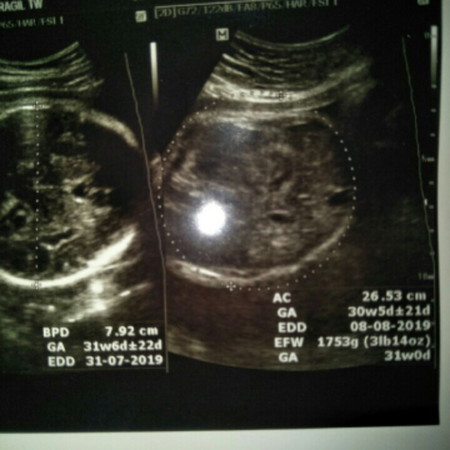

USG

Bun, kemarin saya habis USG. Lupa tanya sama dokternya. Untuk GA nya yg kanan dan kiri itu kok bisa beda gimana ya bun? Bunda yg tau mohon penjelasannya yaa??

Saya juga gitu bun GA nya beda kanan kiri